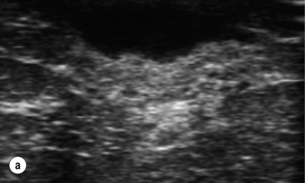

Due to the difficulty of predicting the presence of pus within an inflamed breast, ultrasound with or without aspiration should be performed.71 The need for open drainage in breast abscesses has been superseded by the use of aspiration.7274

This has allowed management of breast infection to become outpatient based. Protocols validated within the Edinburgh Breast Unit have demonstrated that few if any breast abscesses require incision and drainage under general anaesthesia.75 All abscesses should be assessed by ultrasound and if pus is present the surgeon or radiologist aspirates this, usually under ultrasound guidance (Figs 17.8 and 17.9). Patients are reviewed every 2–3 days and any further collections aspirated until no further pus forms. Drainage of pus by making a small stab incision in the skin under local anaesthesia is performed in patients where the overlying skin is thinned or necrotic (Fig. 17.10). The incision to drain any breast abscess should be just large enough to allow the pus to drain (1 cm or less), which minimises later scarring. Ultrasound provides a simple method for differentiating an abscess from cellulitis, allows assessment of any loculation, which is rare, and permits complete aspiration of all pus. Experience in the Edinburgh Breast Unit of using ultrasound to assist aspiration of breast abscesses is that it is quick and simple to learn and use. Local anaesthetic (1% lignocaine with 1:200 000 adrenaline) is injected into non-inflamed skin away from the abscess and along the needle track and is then irrigated into the abscess cavity. Aspiration is then relatively painless and the local anaesthetic helps if the pus is thick by diluting the pus to allow aspiration. Periareolar non-lactational abscesses can be treated and cured by repeated aspiration. Due to the recurrent nature of periareolar infection, recurrent abscess formation is common and in such patients when all signs of acute infection have settled, which takes at least 6 weeks, careful surgical excision of any residual abscess and affected ducts is often required. A mammary duct fistula (a connection between the infected and damaged duct and the skin, usually at the edge of the areola) develops in up to one-third of patients after incision and drainage of a periareolar abscess.76 Fistulas require definitive surgical management. Options include fistulotomy, cutting down on a probe into the fistula and allowing healing by secondary intention, which is painful after surgery and produces an ugly scar, and fistula excision and primary closure. Excising a fistula is easier through a radial scar, but circumareolar incision produces the best cosmetic outcome. Complete excision of the granulation tissue lined tract (plus the affected ducts under the nipple) and primary closure requires antibiotic cover (Fig. 17.11). There is a high risk of recurrence in the presence of postoperative wound infection.77

image

Figure 17.8 Aspiration of abscesses under ultrasound guidance. (a) Ultrasound view of a breast abscess. (b) The needle can be seen entering the abscess on the right, allowing aspiration to be performed.